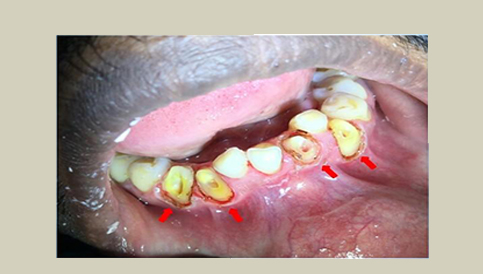

Scaling and Polishing

Dental Crown Lengthening